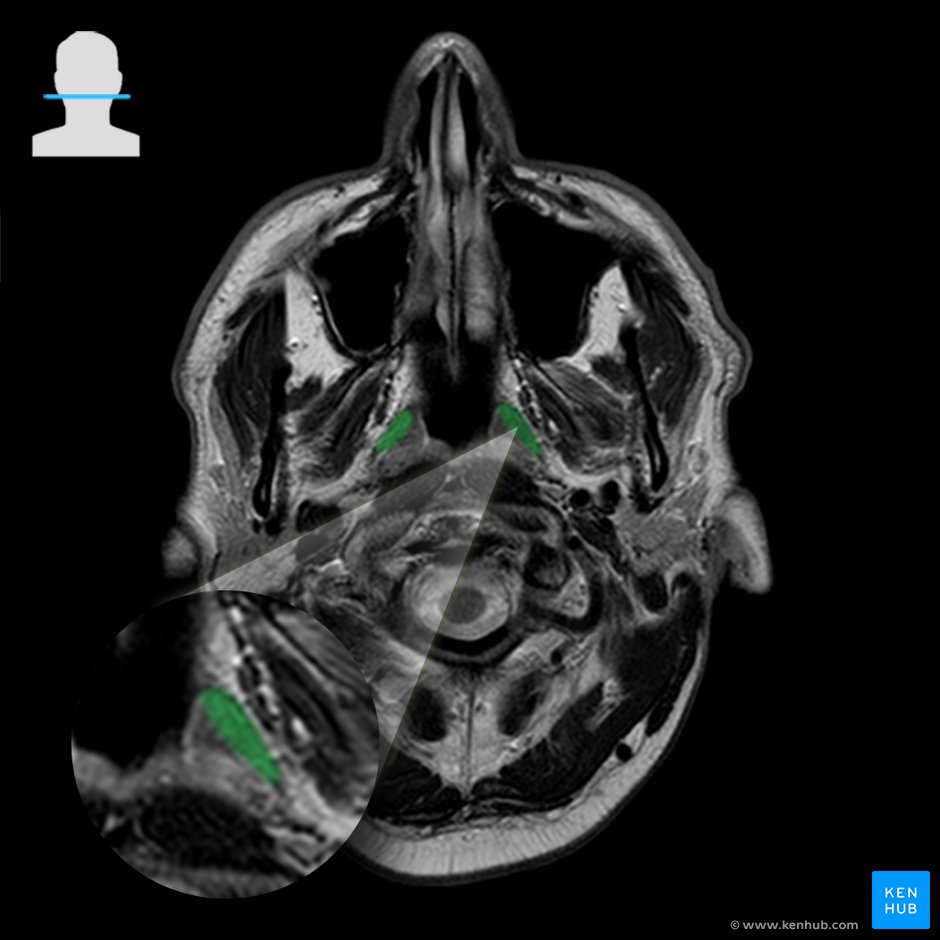

Tensor veli